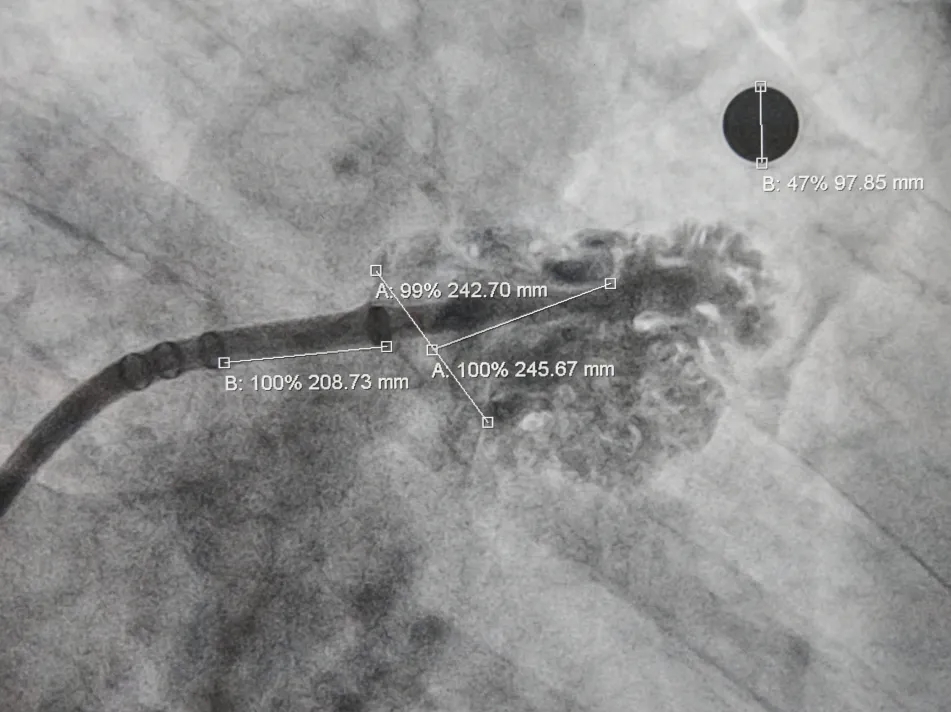

术中DSA肝位造影并测量心耳大小:菜花型左心耳

开口24.3mm,深度24.7mm

该心耳为菜花型,此类心耳一般多为囊袋状多分叶,术前造影评估远端梳状肌较为发达,开口24.3mm,深度24.7mm,深度足够,建议选择LAFDQ-26封堵器进行封堵。

术前结合CT以及术中造影评估左心耳开口24.3mm,深度24.7mm,术中考虑心耳开口和深度充足,可利用心耳空间进行退鞘释放封堵器,使封堵器完全封堵左心耳。术中调整封堵器在心耳内的位置形态,确保封堵器放置位置合适,且牵拉稳固,术后封堵器形态完整,未见残余漏。本病例展开后即刻造影,平口封堵,上下缘不留残腔。封堵器压缩比为10%,压缩合适,术中符合PASS原则,释放封堵器,术后封堵器稳固锚定在心耳壁,封堵器与心耳紧密贴合,无过度扩张风险,显著提升封堵完整性。